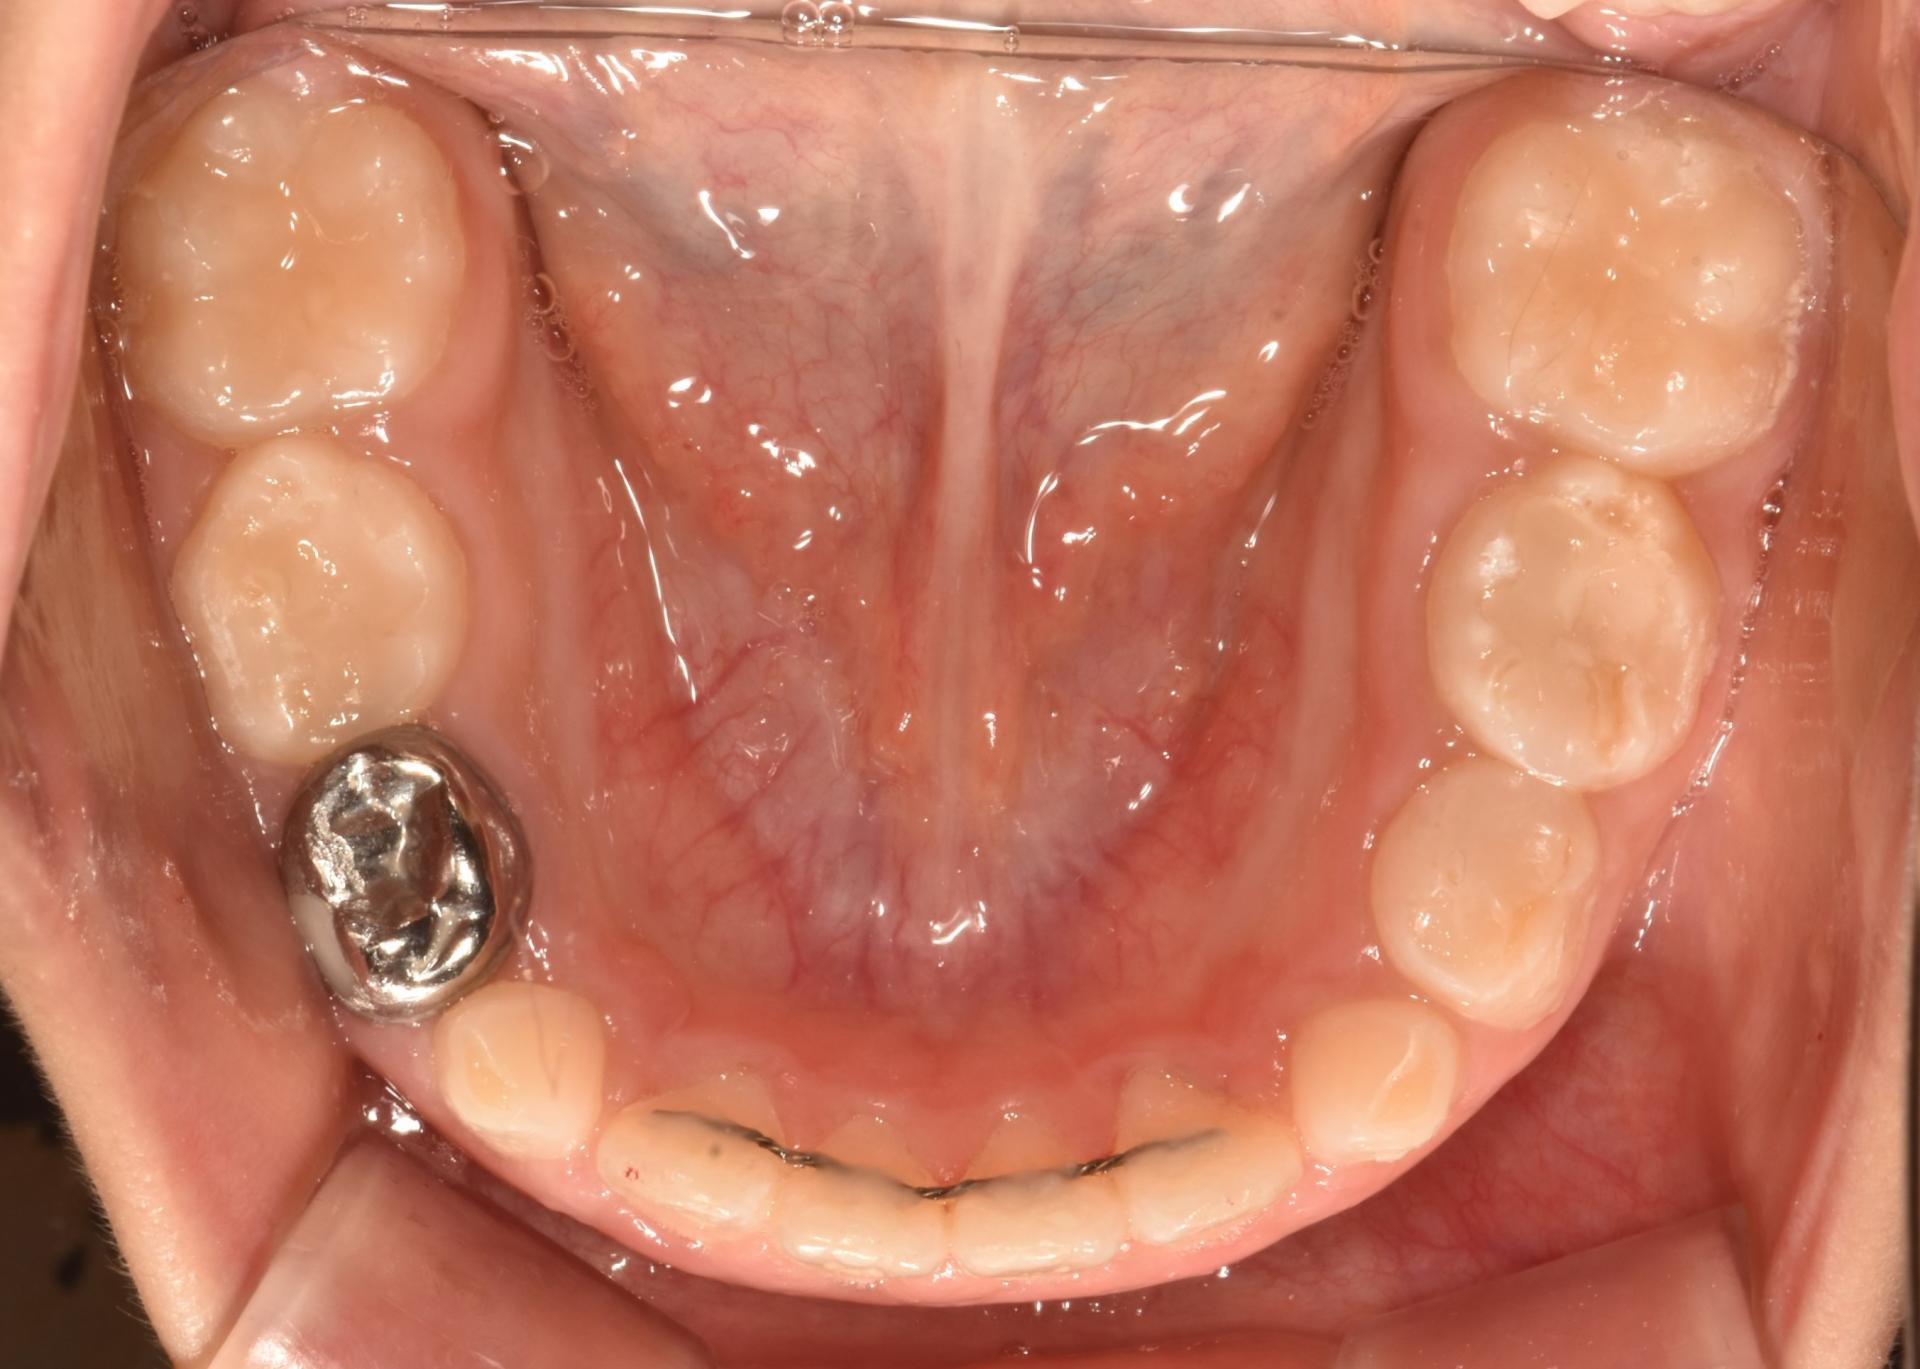

초진입니다. 위아래 앞나의 공간부족으로 이가 삐뚤뺴뚤 나고있고, 앞니도 뻐드려져있네요.